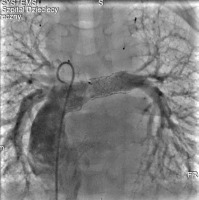

Cardiac catheterisation revealed a significant collateral vessel from the left inferior thyroid artery supplying the left lung and additional collateral vessels arising from the left (LIMA) and right (RIMA) internal mammary arteries supplying both lungs (Figure 1). The Fontan tunnel measured 14.1 mm at its junction with the IVC, widening centrally to 26 mm, and tapering to 10.9 mm at the junction with the pulmonary arteries. No fenestration was identified. The stent in the left pulmonary artery measured 9.8 mm proximally, increasing to 11.2 mm distally (Figure 2). During the procedure, an Amplatzer Vascular Plug successfully occluded the collateral vessel from the left inferior thyroid artery to the left lung, and vascular coils were placed in the RIMA and LIMA. Additionally, a 6-mm Valeo stent was implanted to create a new fenestration (Figure 3).

Figure 3

Angiogram of the pulmonary arteries and Fontan tunnel. The stent in the pulmonary artery was re-dilated, and a 6-mm Valeo stent was implanted to create a new fenestration